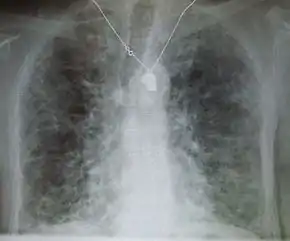

Lung

Side effects of oral amiodarone at doses of 400 mg or higher include various pulmonary effects.[17] The most serious reaction is interstitial lung disease. Risk factors include high cumulative dose, more than 400 milligrams per day, duration over two months, increased age, and preexisting pulmonary disease. Some individuals were noted to develop pulmonary fibrosis after a week of treatment, while others did not develop it after years of continuous use.[17] Common practice is to avoid the agent if possible in individuals with decreased lung function.

The most specific test of pulmonary toxicity due to amiodarone is a dramatically decreased DLCO noted on pulmonary function testing.